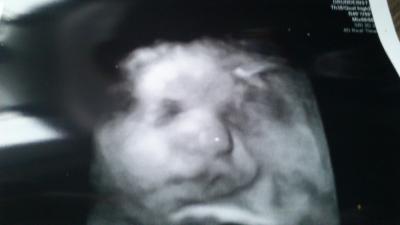

Hallo zusammen, heute morgen hatte ich meinen letzten FA Besuch, jetzt wird nur noch CTG geschrieben. Soweit ist alles ok. Der "kleinen" Maus geht es gut. Sie ist jetzt ca. 50 cm groß und 3380 g schwer. Muttermund ist fingerdurchlässig. Am Samstag und Montag morgen muss ich dann nochmal zum CTG und am Montag Mittag (12 Uhr) soll sanft eingeleitet werden (38+3 ssw). Mensch bin ich aufgeregt, aber ist auch schön zu wissen den kleinen Schatz bald im Arm zu halten VG Kathi

Bild zu zurück vom letzten FA-Besuch... - Forum für Dezember - Mamis

Hoffe das du deine Maus bald im Arm hast,süßes Bild,man das geht jetzt alles so rasant,...